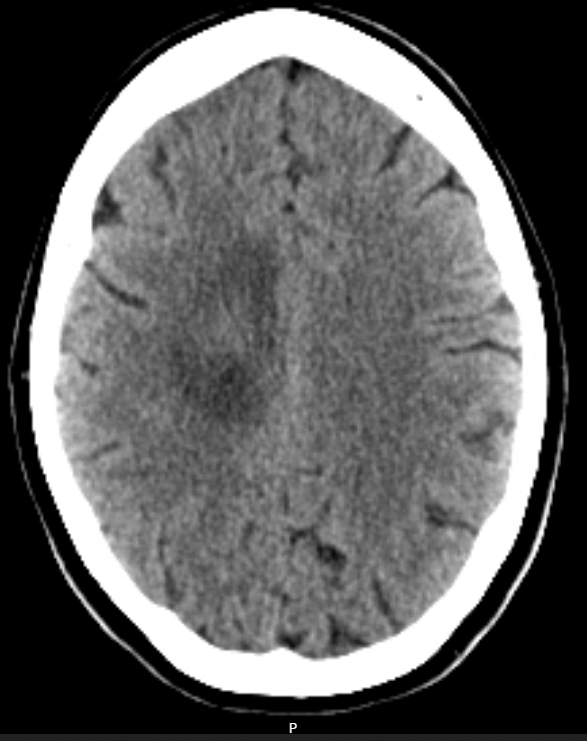

A CT-Brain is urgently booked 2 days later. (Click to open images)

Describe these CT images

Axial slices

Large hypodense space-occupying lesion in the right frontal/pareital lobe

Poorly defined borders

Midline sulcal effacement and minor midline shift

No ventricular obstruction

No obvious signs of raised ICP